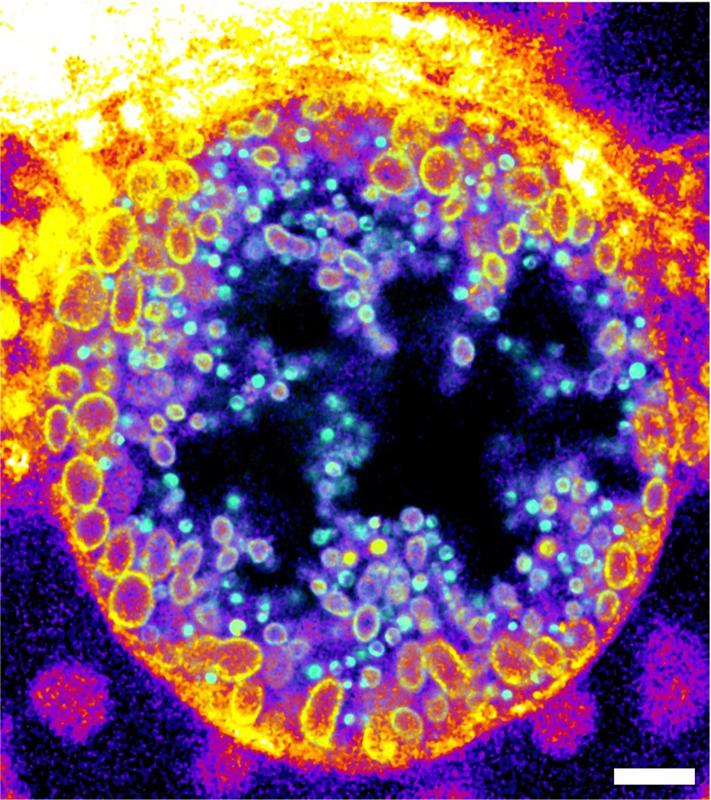

Innerhalb ihrer Wirtszellen bilden Chlamydien eine replikative Organelle, die als Inklusion (Einschluss) bezeichnet wird. Die Forschenden zeigten, dass Chlamydien-Inklusionen hauptsächlich die gespaltenen Formen der trifunktionalen Sphingomyeline enthalten. Mit Hilfe der Expansionsmikroskopie und Click-Chemie beobachteten sie, dass der Anteil der verstoffwechselten Sphingomyelinmoleküle während der Entwicklung von nicht-infektiösen zu infektiösen Chlamydienpartikeln zunahm. Durch die Möglichkeit, diesen Infektionsprozess sichtbar zu machen, können nun neue gezielte Strategien gegen diese Infektionen entwickelt und getestet werden.